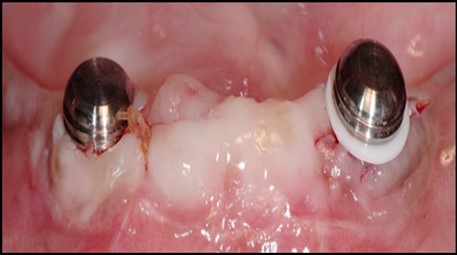

Figure 7.(A) View of 2.0mm and 5.0mm post Locator Abutments with a 2.0mm post. (B) Placement of the Locator Abutment after the well of implant has been cleaned with alcohol on a cotton-tipped applicator.

(A) View of 2.0mm and 5.0mm post Locator Abutments with a 2.0mm post.                             (B) Placement of the Locator Abutment after the well of implant has been cleaned with alcohol on a cotton-tipped applicator.